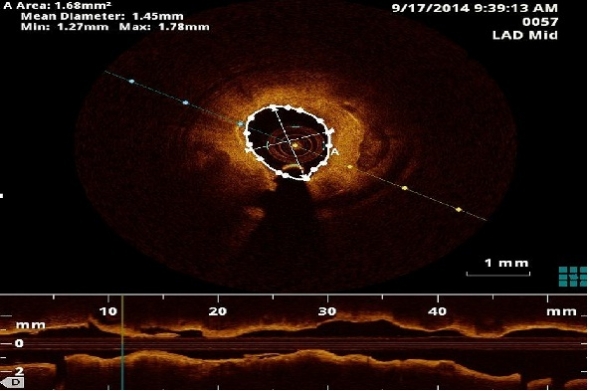

Qual a localização das zonas de um vaso sanguíneo com maior risco de  reestenose após a aplicação de um stent farmacológico? Sirolimus ou  Paclitaxel, qual o mais eficaz? Qual a posição do stent farmacológico  com melhores resultados?

Estas são algumas das questões colocadas em cardiologia para as quais a matemática pode contribuir na procura de respostas.

Nesta  palestra ilustramos como o diálogo interdisciplinar entre a cardiologia  e a matemática pode encontrar solução para questões médicas.